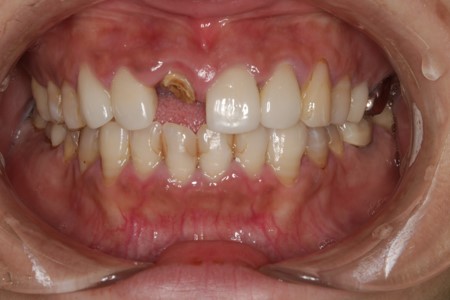

• 治療前

• 治療後